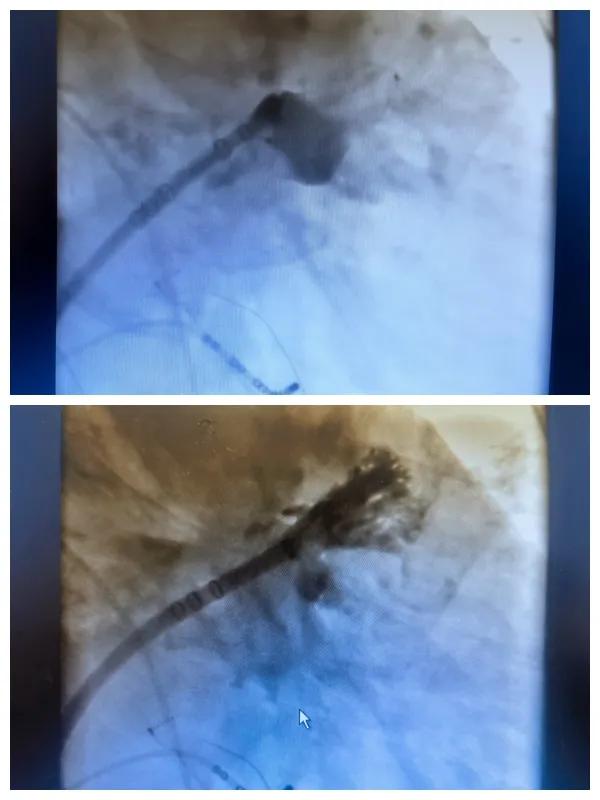

漯河市二院成功開(kāi)展房顫射頻消融術(shù)+左心耳封堵WM FLX一站式手術(shù),再攀“心”高峰!

房顫射頻消融術(shù)+左心耳封堵WM FLX一站式手術(shù)

6月26日,市二院成功為一名老年房顫患者實(shí)施了房顫射頻消融術(shù)+左心耳封堵WM FLX一站式介入治療,標(biāo)志著醫(yī)院在心律失常介入治療領(lǐng)域邁出了嶄新的一步,開(kāi)啟了新的治療篇章。

本次手術(shù)特邀我國(guó)著名心血管內(nèi)科專家、河南省胸科醫(yī)院黨委書記袁義強(qiáng)及血管內(nèi)科七病區(qū)主任黃瓊教授蒞臨指導(dǎo),市二院院長(zhǎng)王瑾帶領(lǐng)心血管內(nèi)科電生理等專家團(tuán)隊(duì)緊密合作,一次性解決了患者房顫、血栓兩大困擾,也使患者告別了終身服用抗凝藥的痛苦,極大地降低了患者的經(jīng)濟(jì)和用藥負(fù)擔(dān)。

為了讓患者得到全面、綜合的治療,經(jīng)過(guò)團(tuán)隊(duì)術(shù)前充分討論,并征得家屬同意,心血管內(nèi)科團(tuán)隊(duì)決定采用目前國(guó)內(nèi)外先進(jìn)的房顫射頻消融術(shù)+左心耳封堵WM FLX一站式介入微創(chuàng)手術(shù)來(lái)治療老人的疾病。整個(gè)手術(shù)過(guò)程圓滿順利,術(shù)后何大爺各項(xiàng)體征正常,蘇醒后順利返回病房。